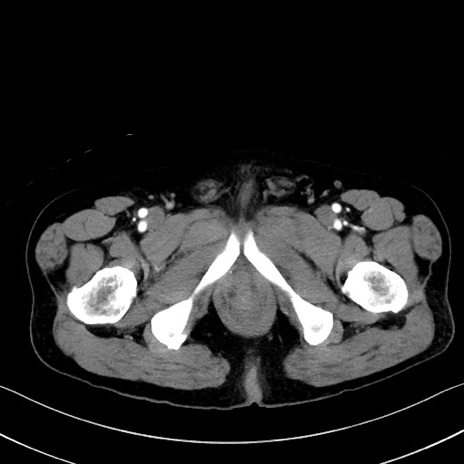

症例35(横断像)

【症例】70歳代 男性

【主訴】腹部膨満、嘔吐

【現病歴】昨日より腹部膨満感出現。本日増悪し、仙痛出現。嘔吐あり、受診。

【既往歴】糖尿病、胆摘後

【身体所見】BP 149/80mmHg、HR 74/min、BT 35.9℃、腹部:膨満、軟、圧痛なし。腸雑音減弱あり。上腹部正中切開瘢痕あり。

【データ】WBC 13500、CRP 1.72